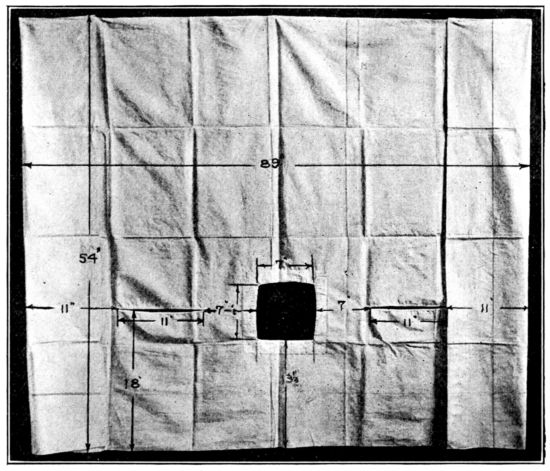

| 109. | Forceps sheet used in Fig. 108 | 303 |

| 110. | Two types of leggings for obstetrical use | 304 |